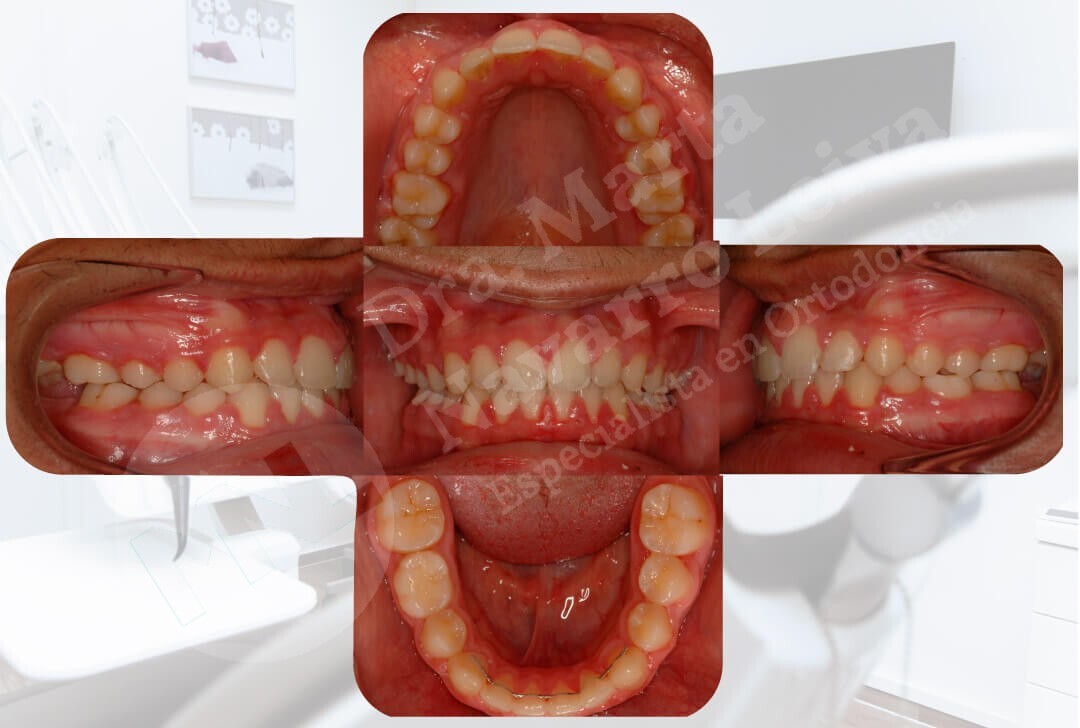

Falta de espacio para la buena colocación y alineación de los dientes.

Deslice libremente el separador en cada uno de los casos para ver las diferencias entre maloclusión y resultado de ortodoncia.

Antes

Antes